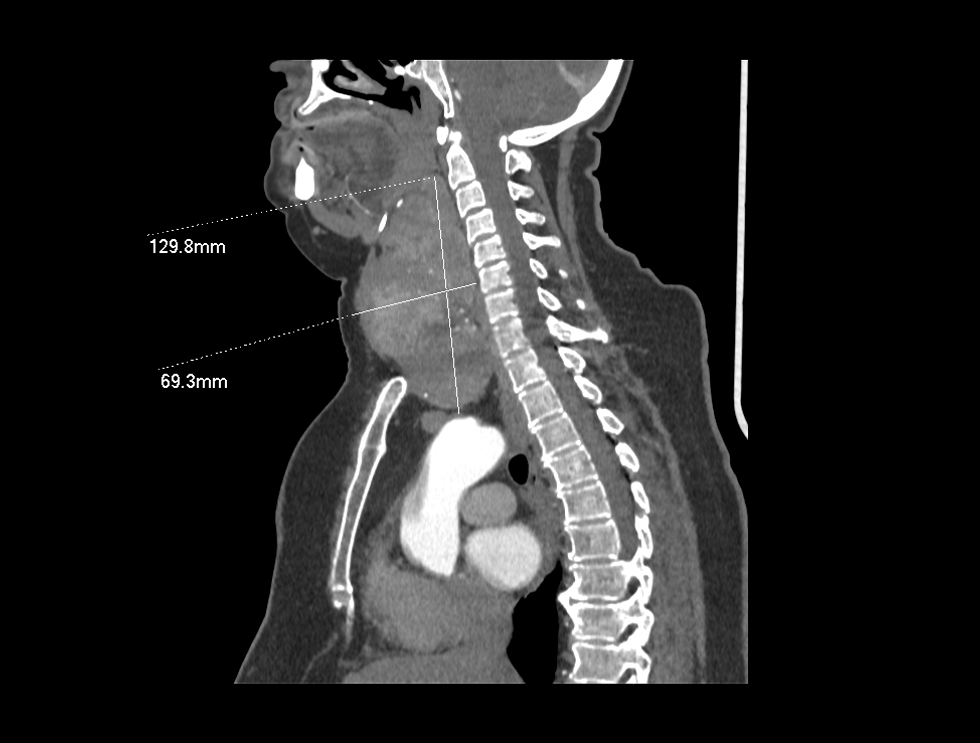

Patologjia e gjëndrës tiroide mund të manifestohet në formën e ndryshimeve në strukturën ose në funksionin e saj. Në grupin e sëmundjeve të gjëndrës tiroide përfshihet edhe gusha, e cila zakonisht manifestohet si rritje e vëllimit të gjëndrës tiroide në pjesën e përparme të qafës.

Gusha është pa dhimbje, por nëse rritet shumë, mund të shkaktojë vështirësi në gëlltitje, ndryshime në zë, kollë dhe vështirësi në frymëmarrje. Në këtë rast, e vetmja zgjidhje për trajtim është ndërhyrja kirurgjikale.

Në Klinikën Zhan Mitrev, është diagnostikuar dhe e mënjanuar në mënyrë kirurgjikale gusha/struma me përmasa të mëdha tek një paciente me vështirësi në frymëmarrje dhe gëlltitje.